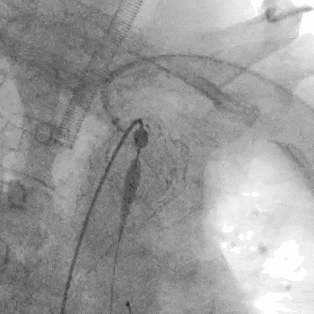

2.右股动脉置鞘交换Lunderquist导丝后,经右侧股动脉上华脉泰科PTBS3834180胸主动脉覆膜支架至左颈总动脉后缘位置,完全覆盖病变段,释放支架。

泥鳅导丝怎么用符伟国/王利新教授团队:0.035"普通泥鳅导丝进行胸主动脉弓上分支原位开窗的病例分享_https://www.jmylbn.com_新闻资讯_第10张

近端定位LCCA根部后缘

泥鳅导丝怎么用符伟国/王利新教授团队:0.035"普通泥鳅导丝进行胸主动脉弓上分支原位开窗的病例分享_https://www.jmylbn.com_新闻资讯_第11张

释放大支架

泥鳅导丝怎么用符伟国/王利新教授团队:0.035"普通泥鳅导丝进行胸主动脉弓上分支原位开窗的病例分享_https://www.jmylbn.com_新闻资讯_第12张

释放近端裸支架